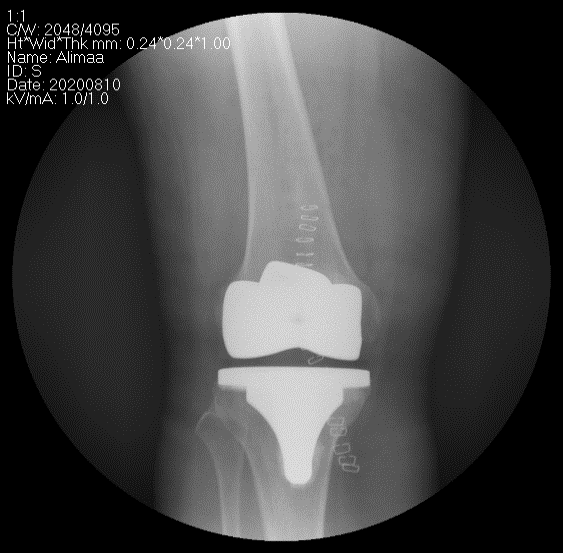

Рентген, эгц урдаас харуулсан байдал

Рентген, хажуугаас харуулсан байдал